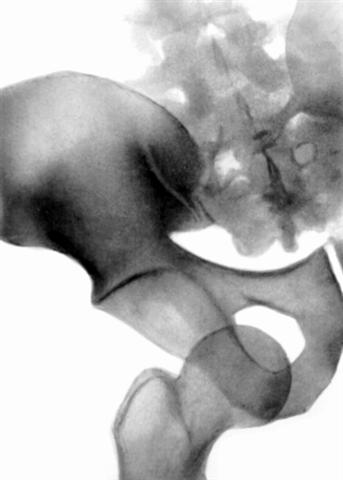

Рис. 13а). Рентгенограмма тазобедренного сустава (прямая проекция) при травматическом вывихе правого бедра.